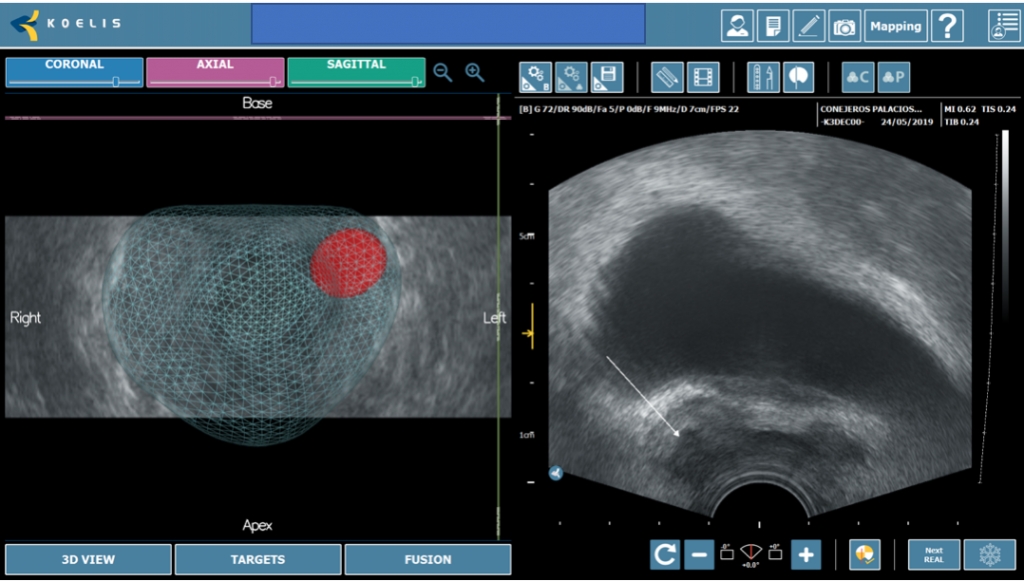

La próstata se escanea con la sonda de US. El operador define los contornos de la próstata y delinea las lesiones sospechosas a tratar en las imágenes de Resonancia. Los límites de la próstata se definen en la imagen en tiempo real de la próstata obtenida con la sonda trans-rectal del dispositivo. El software ejecuta automáticamente una “fusión elástica” de los dos volúmenes definidos, lo que conduce a una combinación tridimensional (3D) perfecta del volumen de RM con el volumen de la próstata en US. La misma fusión 3D se aplica al área sospechosa previamente identificada en la resonancia magnética y/o Biopsia por fusión que, por lo tanto, se puede identificar correctamente en la imagen en vivo de US. (Figura 3-4).

La terapia focal permite la preservación de la mayoría de tejido prostático normal, incluyendo los haces neurovasculares y mecanismos de la continencia urinaria. Adicionalmente, los avances en mpMRI y los mapas de Biopsias por fusión, definen precisamente la lesión objetivo y usando HIFU uno puede tratar solamente esa lesión o esa área a fin de mantener un margen de seguridad oncológica (Figura 4).